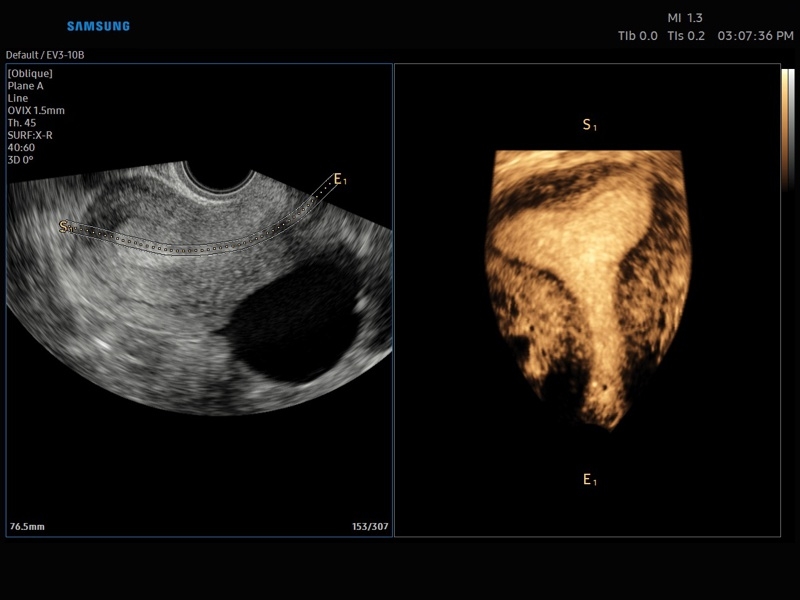

• OVIX(Oblique View eXtended) - получение фрагмента трехмерного изображения (в виде нескольких полупрозрачных сканов, последовательно наложенных один на другой) в направлении произвольного косого среза трехмерного объекта исследования.

• Система Static 3D - трехмерное сканирование объемными датчиками в статическом режиме в серой шкале и восстановление объемной структуры сосудов в режиме цветного / энергетического допплера).

• СистемаLive 3D- трехмерное сканирование объемными датчиками в реальном масштабе времени (4D).